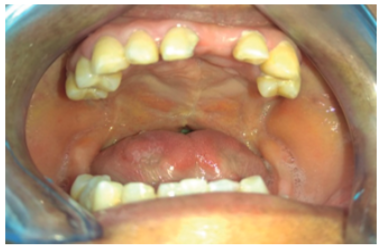

A través de la Fundación Operación Sonrisa Ecuador, la paciente fue sometida a palatoplastia con resultados favorables (figura 3).

Figura 3. Palatoplastia

Fuente: historia clínica del paciente

Posterior a la recuperación posquirúrgica, se retomaron los ejercicios para corregir las praxias bucofonatorias sin reportarse mejoría importante durante los tres primeros meses; a partir de cuales, la paciente evidenció una mejora significativa llegando a obtener un rango medio alto de 92/110 y 12/15 según los resultados de los instrumentos de evaluación mencionados. De igual manera, la capacidad de deglución se incrementó en un 90%.